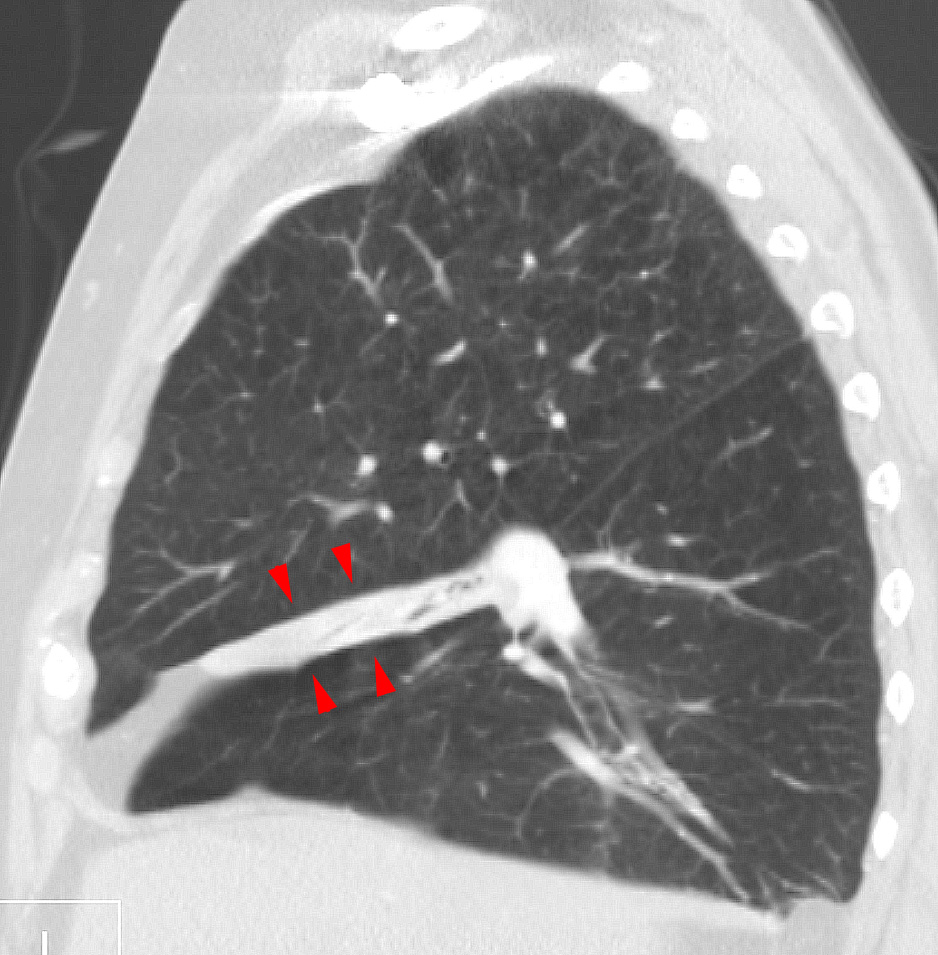

임상적으로 유의미한 무기폐는 일반적으로 흉부 엑스레이에서 관찰 가능하며, 폐의 불투명화 및/또는 폐 용적 감소와 같은 소견을 보일 수 있다. 수술 후 무기폐는 양쪽 기저부에서 나타나는 양상을 보인다. 무기폐의 원인이 임상적으로 명확하지 않은 경우 흉부 CT 또는 기관지 내시경이 필요할 수 있다.[10] 무기폐의 직접적인 징후로는 엽간 열구 및 흉강 내 이동성 구조의 변위, 영향을 받지 않은 동측 폐엽 또는 반대쪽 폐의 과도한 팽창, 그리고 허탈된 폐엽의 불투명화가 있다.[10] 흉부 엑스레이에서 임상적으로 유의미한 소견 외에도, 환자는 횡격막의 상승, 기관, 심장 및 종격동의 이동, 폐문의 변위 및 육아종의 이동과 같은 간접적인 징후와 증상을 나타낼 수 있다.[10]

시상 단면 CT 재구성에서 중간엽 무기폐